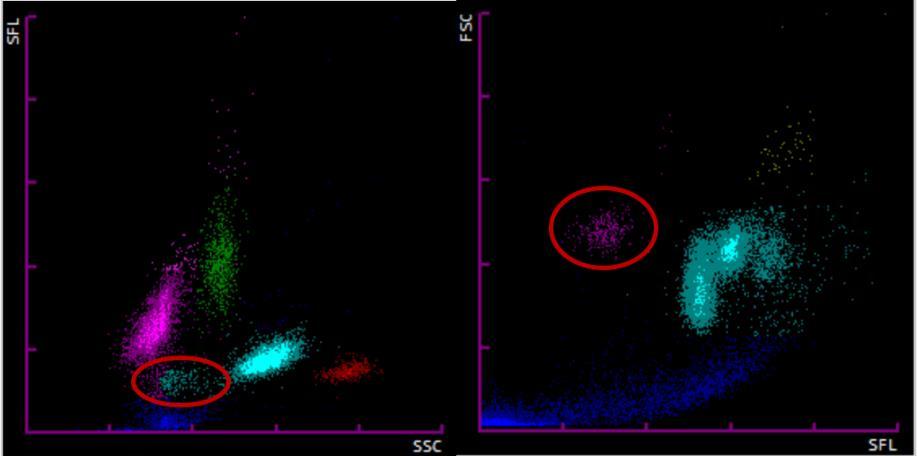

La tecnología de Sysmex se fundamenta en la citometría de flujo con fluorescencia, en la que se utilizan fluorocromos que se impregnan en las células tras sufrir estas un proceso de permeación de su membrana celular. Mediante una luz láser enfocada a las células se obtienen tres parámetros: Forward Scatter Light (FSC), Side Scatter Light (SSC) y Side Fluorescence Light (SFL), que se correlacionan con el

Figura 1. Scattergramas de Beckman Coulter (A) y Sysmex (B). Elaboración propia

tamaño celular, la estructura celular interna y el contenido en ácidos nucleicos respectivamente. Ambas tecnologías permiten obtener unos gráficos de dispersión conocidos como scattergramas que clasifican las poblaciones celulares dentro de las categorías de Neutrófilos, Linfocitos, Monocitos, Eosinófilos y Basófilos. Además, existen alarmas que aparecen cuando el algoritmo matemático que utilizan los equipos supera el valor límite trigger al detectar la presencia de las células anómalas. En el caso de Sysmex, tenemos la posibilidad de generar test adicionales utilizando diferentes reactivos químicos, lo que permite clasificar de forma más precisa diferentes poblaciones celulares.